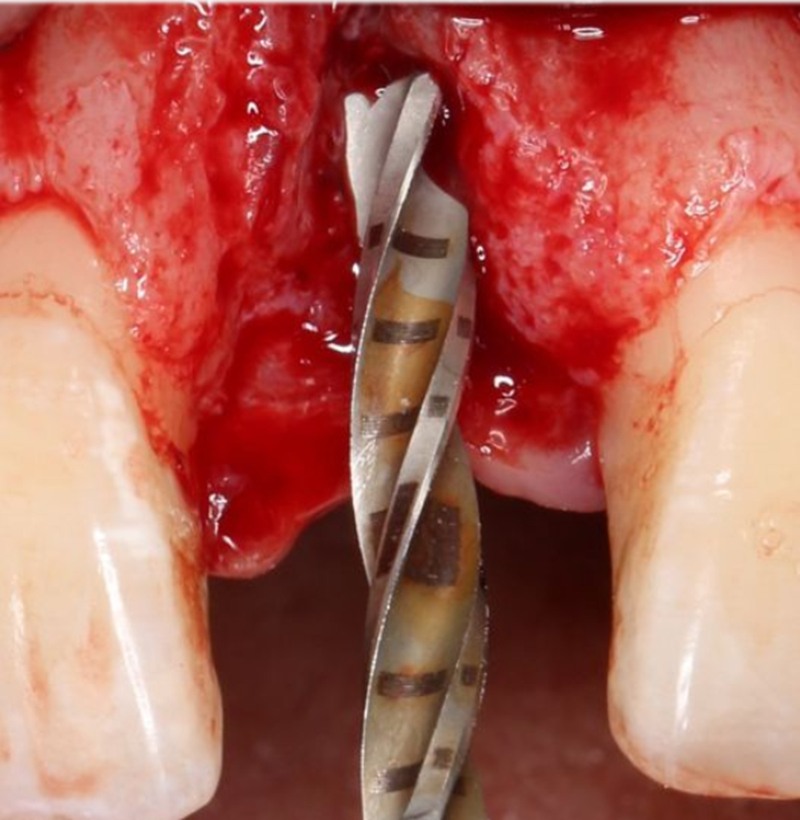

定點

1.4mm小球鉆定點 △

2.3mm中號球鉆打開皮質(zhì)骨

在易植美實時導(dǎo)航系統(tǒng)中,計算機引導(dǎo)球鉆精準按照術(shù)前設(shè)計定位